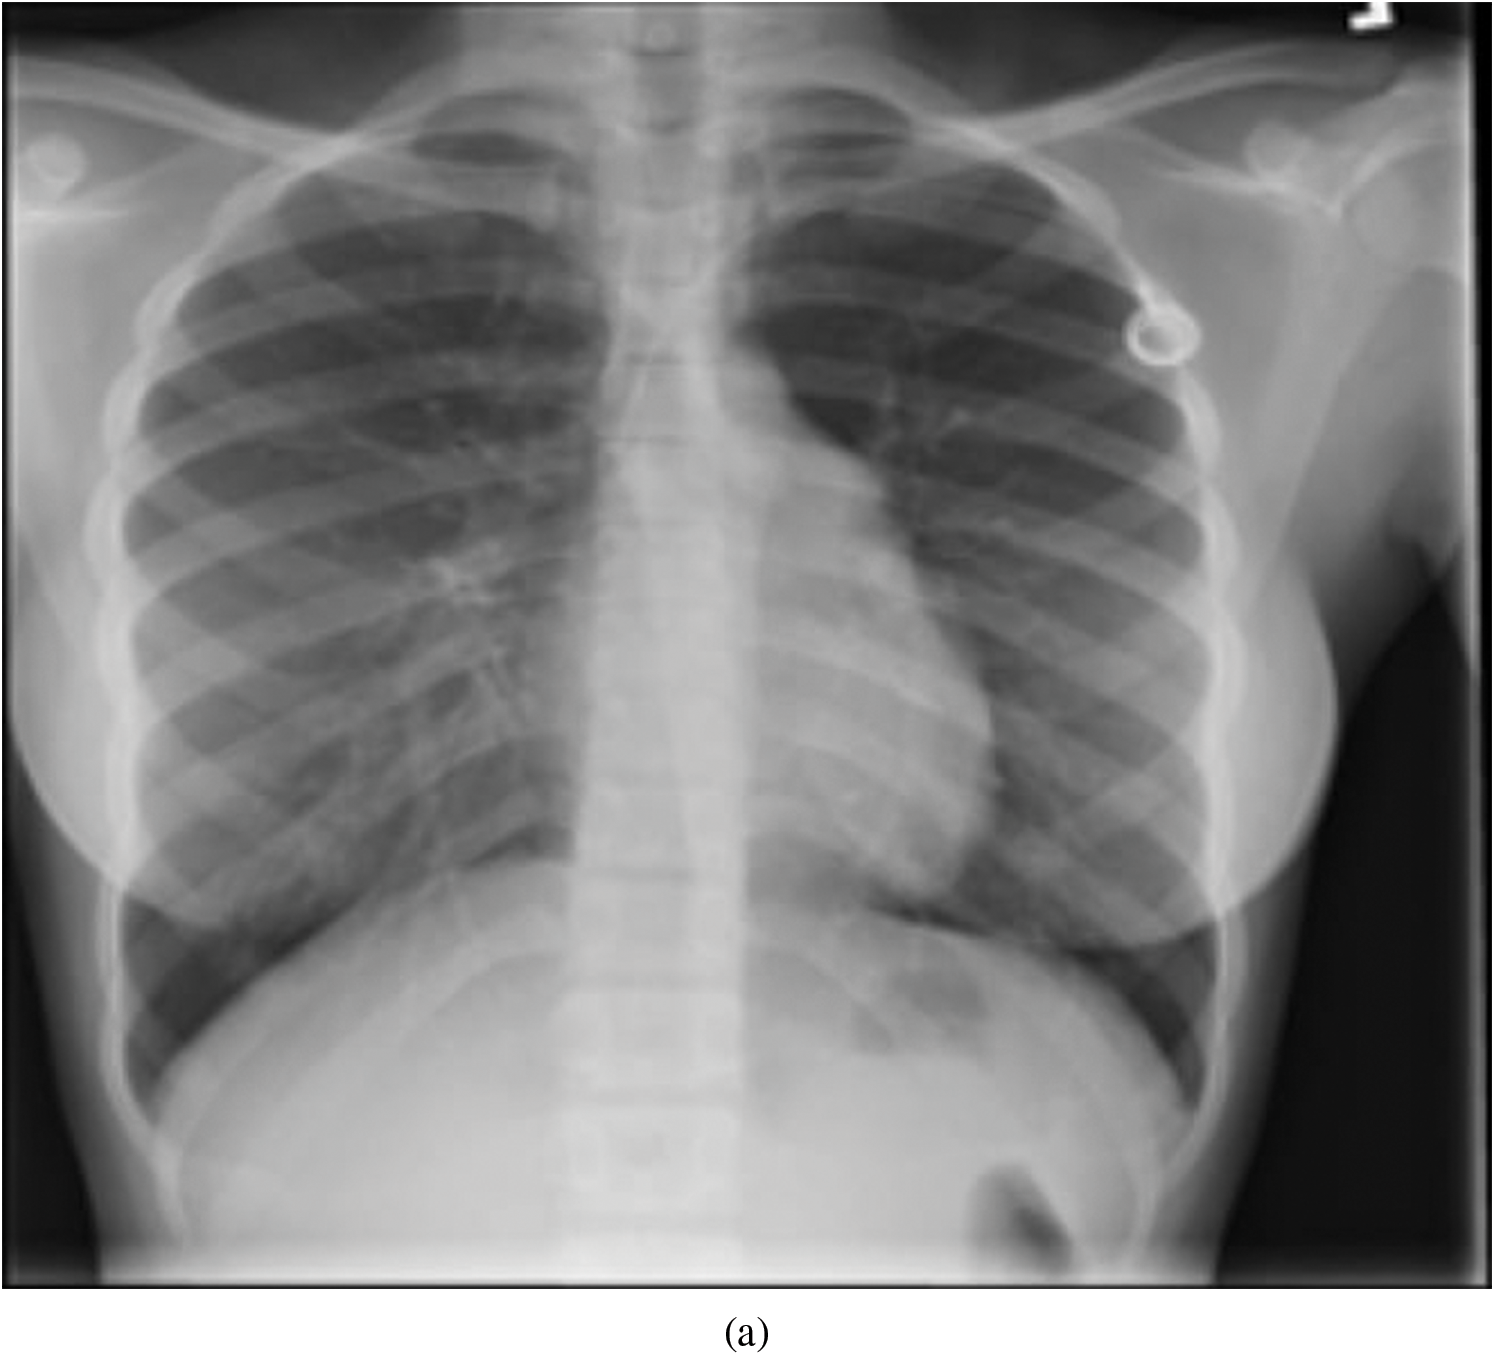

Representative images belonging to the normal, COVID-19, LO, and VP groups are shown in Figs. 2–5, along with their corresponding histograms. The images clearly depict variability in pixel intensities, particularly in and around the lung regions. The visibility of the rib cages is very obvious in the case of the normal and COVID-19 images as shown in Figs. 2a, 2b, 3a and 3b respectively compared to the LO and VP images in Fig. 4a, 4b, 5a and 5b. The visibility of lungs in COVID-19 patients is unclear. The histograms represent different perspectives, with varying distribution of intensities across the four categories, particularly COVID-19, indicating a large presence of high pixel intensities.

Figure 2: Representative image and its corresponding histogram depicting the distribution of pixel intensities of a normal image